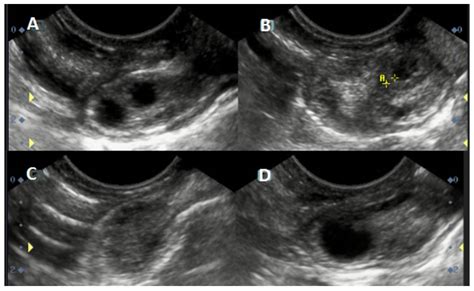

For individuals undergoing fertility treatments like IUI (Intrauterine Insemination) or IVF (In Vitro Fertilization), monitoring the growth of the dominant follicle in the ovary is a standard procedure. Fertility specialists use transvaginal ultrasound to visualize these structures.

It is important to note that while ultrasound is highly accurate, it only provides a snapshot of the size of the follicle. Quality of the egg cannot be determined solely by the size of the follicle.